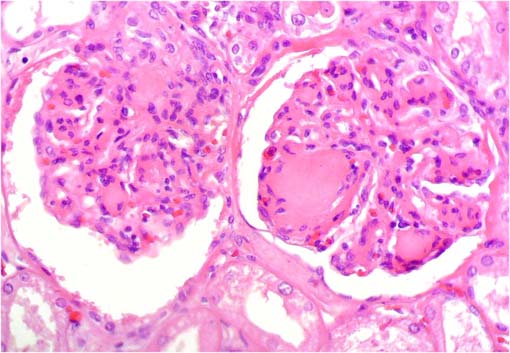

En las siguientes imágenes histológicas

de sus riñones hay una lesión patognomónica. ¿Cuál

es la enfermedad y cuál la lesión patognomónica?

Figura 1.

H&E, X400.